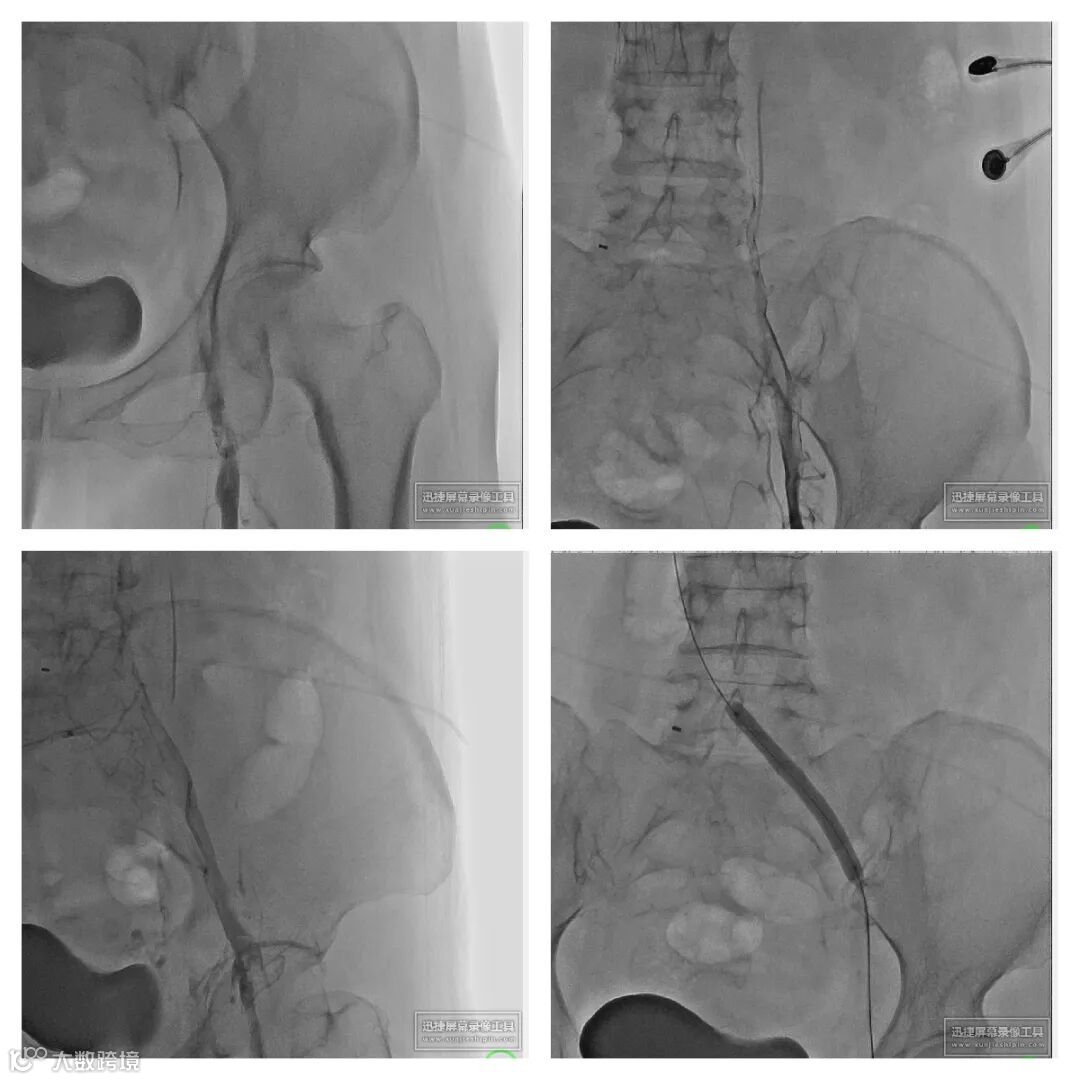

1. 超声引导下穿刺左腘静脉,置入6F鞘管,造影确认。

2. 右股静脉穿刺,造影示:下腔静脉血栓形成。小心通过后放置下腔静脉滤器。

3. 左腘静脉更换Tendfast®14F鞘管,造影示:左下肢全程静脉血栓形成。

4. 送入腾复Tendfast®外周静脉取栓支架,左股静脉拉栓1次,造影显示:左股静脉血流通畅。

5. 左髂静脉血栓负荷较重,通过左髂总静脉后,给予6mm*150mm球囊扩张。

6. 引入Tendfast®外周静脉取栓支架,从左侧髂静脉拉栓2次,造影显示血流恢复通畅。